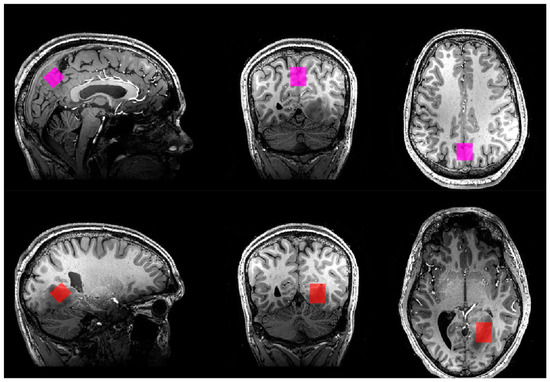

Diagnostic Imaging: Brain | American Journal of Neuroradiology。26,600+ Brain Scans Stock Photos, Pictures & Royalty-Free。Single-Voxel MR Spectroscopy of Gliomas with s-LASER at 7T。eBook使用済みです。Covering the entire spectrum of this fast-changing field, Diagnostic Imaging: Brain, fourth edition, is an invaluable resource for neuroradiologists, general radiologists, and trainees-anyone who requires an easily accessible, highly visual reference on today's neuroimaging of both common and rare conditions. World-renowned authorities provide updated information on more than 300 diagnoses, all lavishly illustrated, delineated, and referenced, making this edition a useful learning tool as well as a handy reference for daily practice.Provides authoritative, comprehensive guidance on both pathology-based and anatomy-based diagnoses to help you diagnose the full range of brain and CNS conditionsFeatures thousands of extensively annotated images, including a large number of full-color illustrations-greatly expanded since the previous edition.#brain #神経 #神経解剖 #神経内科 #脳神経内科 #脳外科 #脳神経外科#脳 #脳解剖 #頭部画像 #頭部解剖 #MRI #頭部MRI #神経画像。m3電子書籍 | 脳神経画像解剖ナビゲーション。書籍としての状態は良好です。医科学大事典 全50巻セット 総額200万 医学本 医療本医科学辞書辞典医大医者

• Diagnostic Imaging: Brain | American Journal of Neuroradiology

• Single-Voxel MR Spectroscopy of Gliomas with s-LASER at 7T